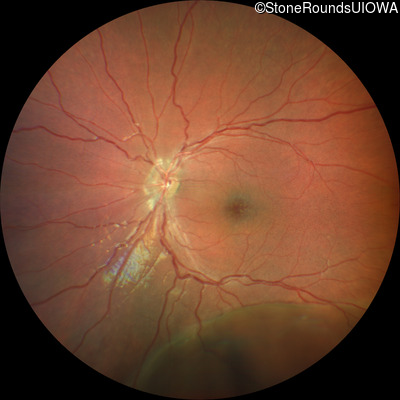

XL Retinoschisis (IIIB1)

Age at visit: 6 years

OD OS

This 6 year old boy began sitting very close to the television at age 2.

Diagnosis & molecular findings

XL Retinoschisis RS1 Tyr93Stop TAT>TAG   XL